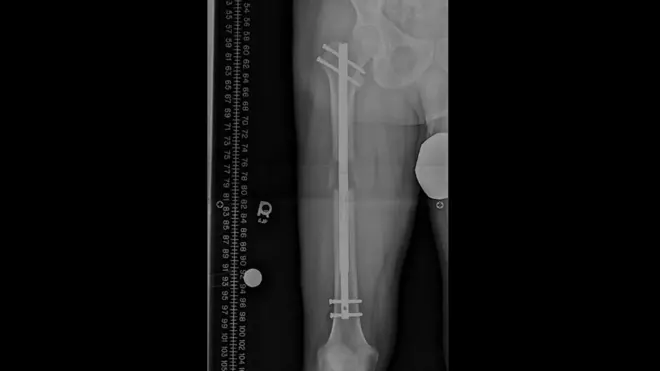

Estuve 32 días en coma. Los primeros diez no me pudieron dar ni un analgésico. Temían que muriera. Todo mi lado izquierdo, incluidas mi cara y mi cabeza, estaban quemados.

Al séptimo día, los dedos de mi mano izquierda se carbonizaron.

El cuerpo de quienes nos quemamos tiende a encogerse, por lo que te tienen que operar muchísimas veces.

Me hicieron 17 cirugías hasta los 19 años.

Ahí decidí no operarme más porque en la última cirugía estuve en coma inducido durante tres días.